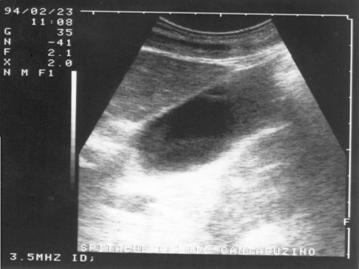

INTARIREA ACUSTICA

Peretele ce

separa o structura lichidiana de o structura solida constituie o interfata.

Deoarece diferenta de densitate dintre cele doua structuri este mare, interfata

este foarte evidenta; la acest nivel producandu-se o reflectare masiva de

ecouri. Interfata ce separa mediul solid de cel lichidian devine astfel foarte

ecogena. Aceasta ecogenitate se propaga pe distante mici, distal de structura

lichidiana in mediul urmator. Cu cat aceasta propagare distala a ecogenitatii

interfetei este mai mare, cu atat este mai mare diferenta de densitate dintre

mediul strabatut (lichidian) si cel ce urmeaza (solid).

Figura 16. Intarire acustica posterioara la nivelul vezicii urinare.

Figura 17.}ntarire acustica posterioara la nivelul V.B.